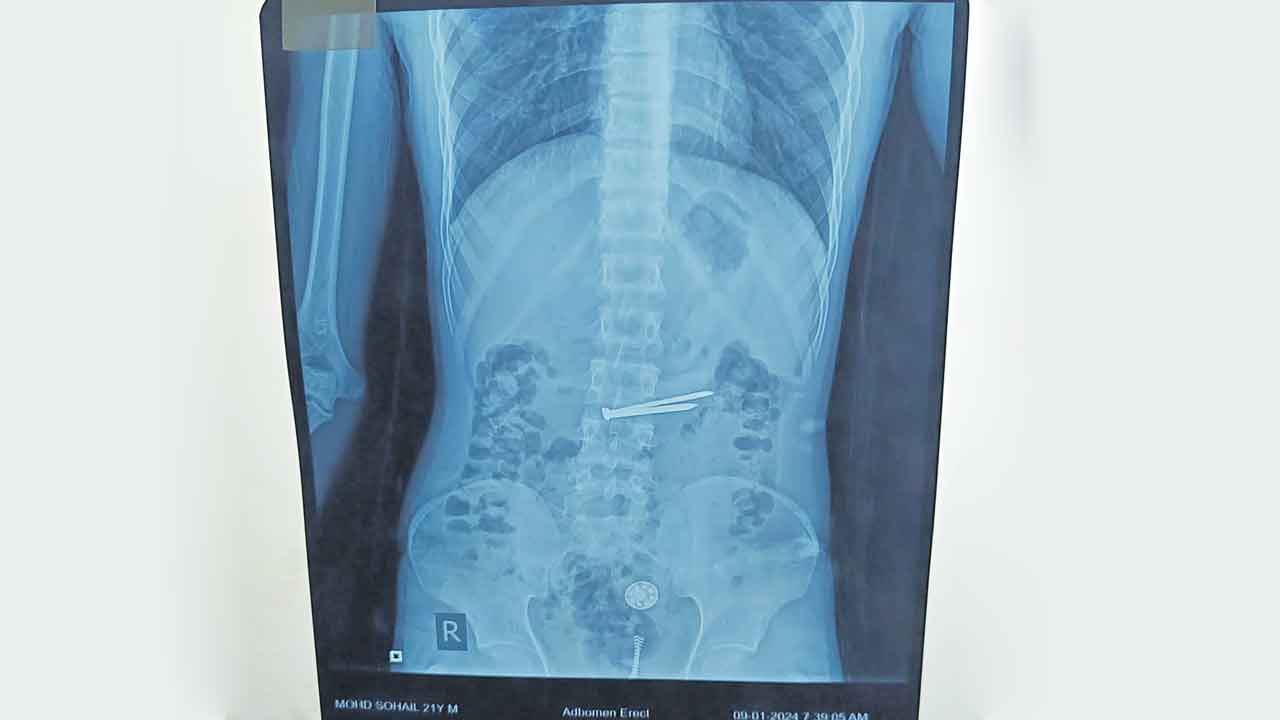

Khaidi patient | చంచల్గూడ జైలులో ఖైదీగా ఉన్న 21 ఏండ్ల మహమ్మద్ సొహైల్ కడుపులో ఉన్న 8 రకాల మెటల్స్ను ఉస్మానియా దవాఖాన వైద్యులు విజయవంతంగా తొలగించి ప్రాణాలను కాపాడారు.